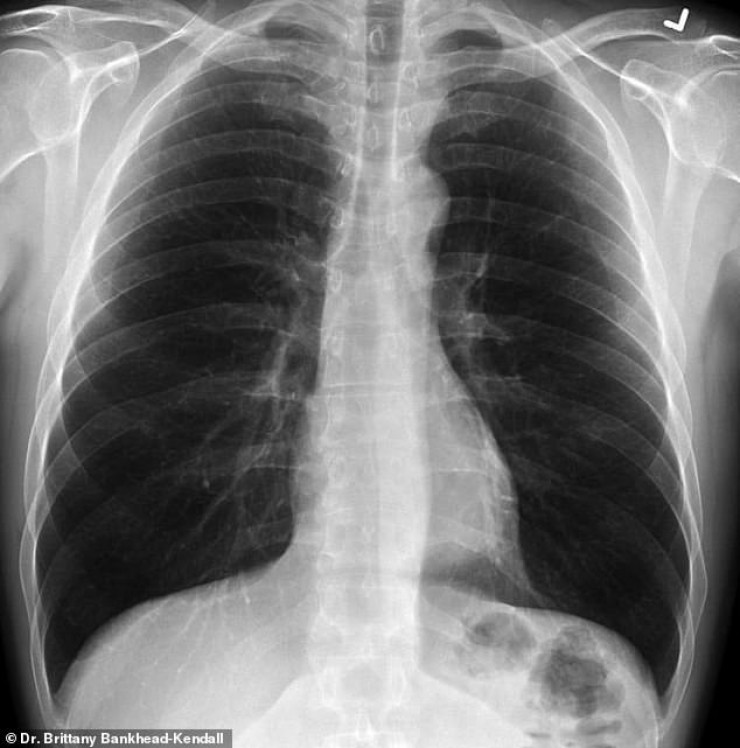

Доцент Центра медицинских наук Техасского технологического университета, доктор Бриттани Бэнкхед-Кендалл показала три рентгеновских снимка легких: здорового человека, курильщика и пациента с коронавирусом.

На рентгеновском снимке здорового пациента много черного пространства, что является показателем нормального количества кислорода.